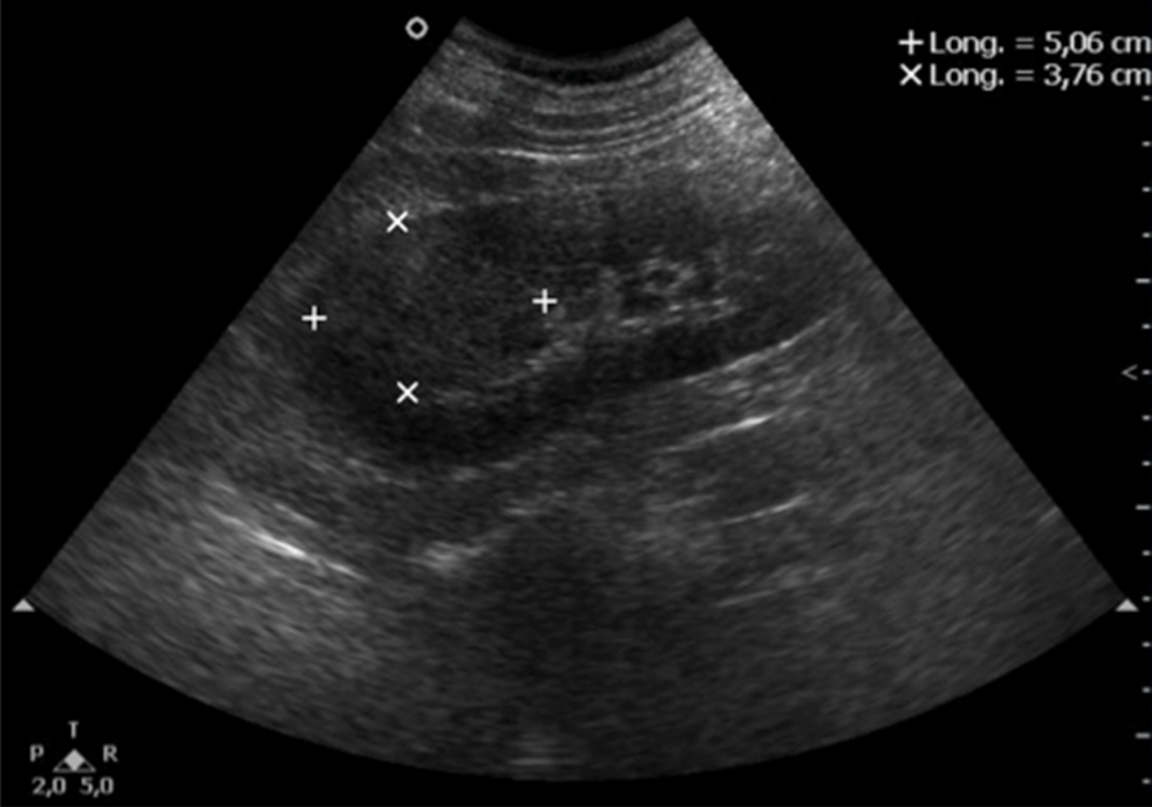

10. kép:

Vese daganat

A vese daganatok sokszor nehezen észrevehetőek ultrahangal, mert a megjelenésük bizonyos esetekben nagyon hasonlít a vese normális állományára. Ebben az esetben a jelölések mutatják a daganat határait. Támpontot ad a diagnózisban hogy a vese kontúrját az eltérés kidomborítja, illetve a vese üregrendszere felé is bedombrodik az elváltozás.